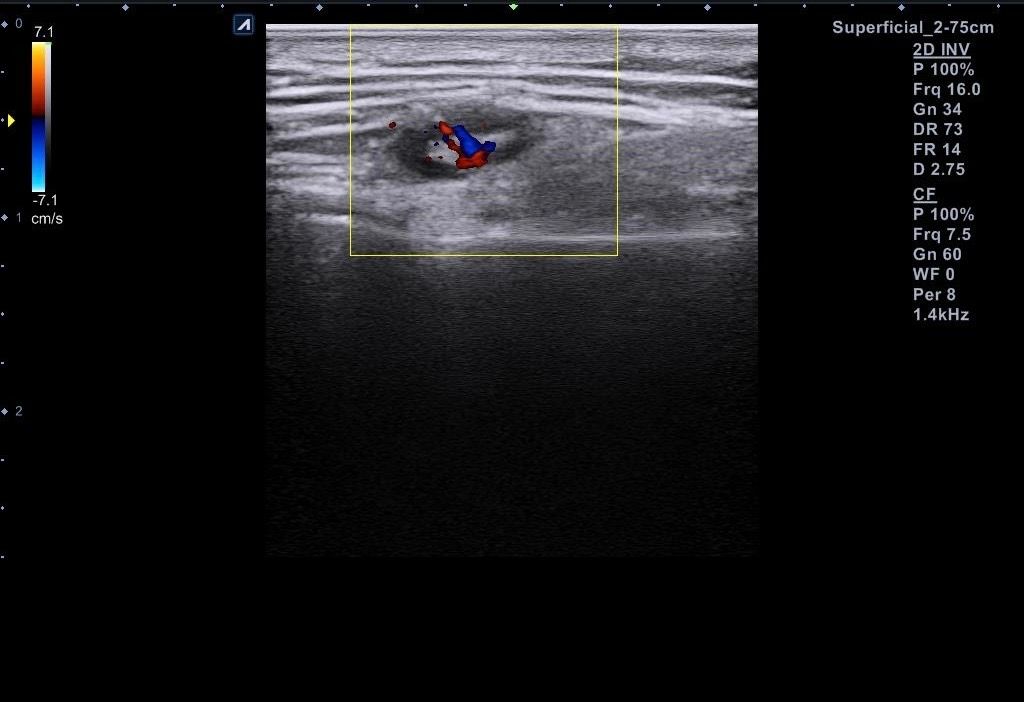

근데 병원에서 지방종이 아니라 임파선 같다고 일단 초음파 본다고 하시고 초음파를 봤는데 의사선생님이 귀 옆에 있는 임파선은 괜찮은데 아래에 있는 임파선이 초음파로 볼때 모양이랑 뭐가 조금 이상하다고 하시면서 대학병원가보라고 소견서를 써주셨습니다 (소견서랑 초음파사진 첨부할게요) 설명들을때 기억상으로는 1 2번째 초음파사진이 귀 아래였던 거 같아요

• 1번 째 사진

• 2번 째 사진

• 3번 째 사진

• 4번 째 사진

• 5번 째 사진

• 6번 째 사진